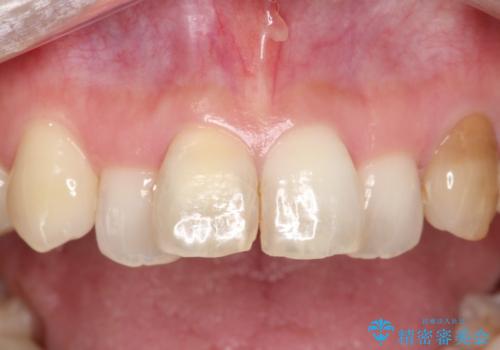

汚れた仮歯が気になる 前歯のオールセラミッククラウン

【オールセラミック】前歯の色を変えたい。

見栄えの悪い仮歯 前歯のオールセラミック治療